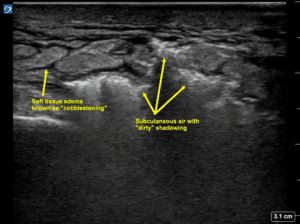

A high-frequency linear probe was used to evaluate the plantar aspect of the patient’s foot. The images revealed several small linear hyperechoic lesions in the subcutaneous layers of the foot exhibiting serpiginous motility (Figure 1). The subcutaneous tissue shifted throughout the migration process. Color Doppler was applied to confirm the moving echogenic lesions were not vasculature structures (Figure 2). The contralateral foot was also scanned for comparison and there was an absence of these motile structures in the epidermis.

Cutaneous larva migrans can be diagnosed solely on a patient’s clinical presentation, however, additional studies may help confirm the diagnosis. Serological tests, such as enzyme-linked immunosorbent assay, can detect specific antibodies against the causative parasites [7]. As well, skin biopsy can be performed to identify the presence of larvae in the skin, but it may be inconclusive, rather invasive, and unnecessary. In other cases, imaging studies like X-rays may be employed to visualize the larvae in visceral tissues [8]. Optical coherence tomography has been reported to be an effective minimally invasive tool to rapidly detect CLM [9]. However, it is not widely available in the ED and is rarely used outside of an ophthalmology office. Although dermoscopy has been used to detect these cutaneous parasites, most EDs do not carry these devices. In a recent study, reflectance confocal microscopy confirmed a larva burrow, described as a hyporeflective disruption of the normal honeycomb pattern in the epidermis [6]. As one can imagine, these devices are more commonly found in dermatology offices and are not typically stocked in most EDs. Interestingly, a high-frequency US was also utilized in that same study. A cylindrical mass and shadowing were revealed which the authors believed may have corresponded to the parasite and larva burrow [6].

There are limited studies demonstrating cutaneous larva migrans with minimally invasive imaging tools in pediatric patients in the ED. In contrast to other imaging modalities, POCUS is a valuable noninvasive portable imaging tool, available in most EDs. It has many clinical applications, including distinguishing between different soft tissue complaints. This case report features POCUS used to detect cutaneous larva migrans. We highlighted motile hyperechoic lesions in the epidermal layer of the patient’s foot, utilizing a high-frequency linear transducer. When these hookworms tunnel through the skin, their paths are highlighted as anechoic tracks amid the echogenic base representing the dermis. Unfortunately, the individual larvae were not detected. While visualizing the actual larva may require more effort and time, the parasitic tracks can be detected via US, as seen with our patient. This technique may prove to be even more clinically useful as another case demonstrated that suspected larva diagnosed via US imaging, were normal soft tissue [6]. As more POCUS implementation is used by clinicians who suspect CLM, there will be more images available to compare our images against. This will perhaps give insight to diagnostic criteria for CLM.